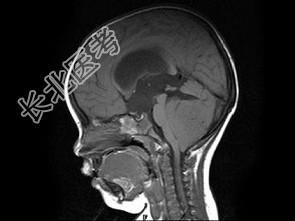

- 单项选择题男,2岁, 头痛、呕吐10余天,MRI检查如图所示, 最可能的诊断为 ( )

A、小脑蚓部髓母细胞瘤

B、星形细胞瘤

C、室管膜瘤

D、生殖细胞瘤

E、未见异常